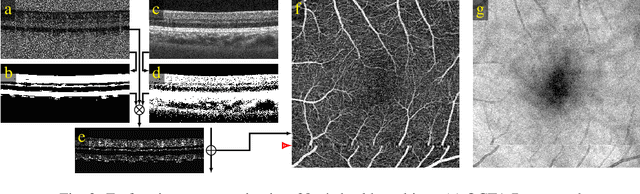

Abstract:We propose a novel method for non-rigid 3-D motion correction of orthogonally raster-scanned optical coherence tomography angiography volumes. This is the first approach that aligns predominantly axial structural features like retinal layers and transverse angiographic vascular features in a joint optimization. Combined with the use of orthogonal scans and favorization of kinematically more plausible displacements, the approach allows subpixel alignment and micrometer-scale distortion correction in all 3 dimensions. As no specific structures or layers are segmented, the approach is by design robust to pathologic changes. It is furthermore designed for highly parallel implementation and brief runtime, allowing its integration in clinical routine even for high density or wide-field scans. We evaluated the algorithm with metrics related to clinically relevant features in a large-scale quantitative evaluation based on 204 volumetric scans of 17 subjects including both a wide range of pathologies and healthy controls. Using this method, we achieve state-of-the-art axial performance and show significant advances in both transverse co-alignment and distortion correction, especially in the pathologic subgroup.